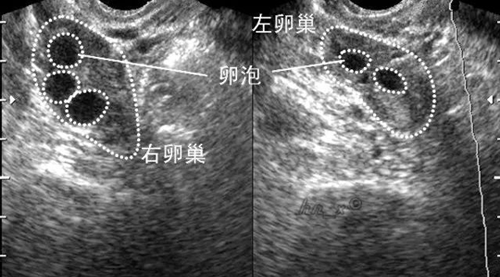

所以的空卵泡就是指没有卵子的卵泡,通常来看它外形与正常卵泡无差别,呈圆形或者椭圆形,直径可达15-30mm左右,但是这种类型的卵泡根本无法受精。

在试管促排前检测到有9个卵泡,但在取卵是却被告知有5个是空的,导致第一次取卵的效果不太理想,想问问下次取卵还会这样吗?空卵泡怎么调理比较好?